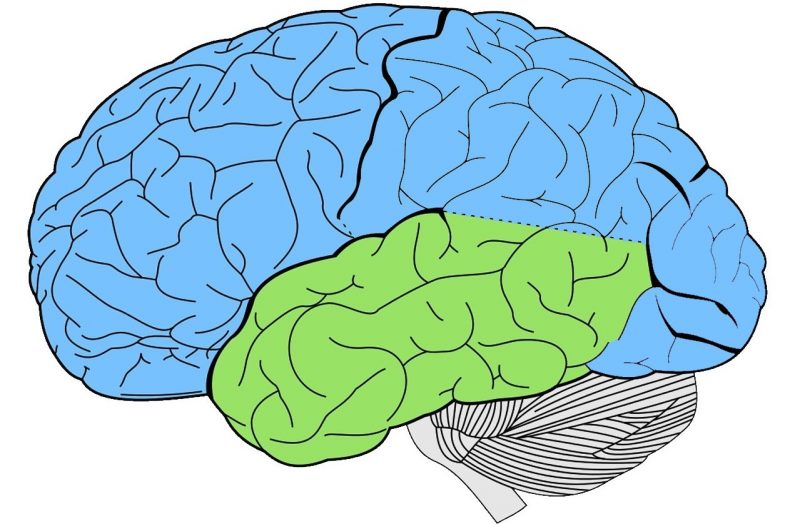

Temporal Lobe Anatomy Location Function Damage Epilepsy

Temporal Lobe Function Anatomy Info

https://anatomyinfo.com/wp-content/uploads/2018/06/temporal-lobe-function-1.jpg

Temporal Lobe SpinalCord

Temporal Lobe The Definitive Guide Biology Dictionary

Temporal Lobe Function Location And Structure

Temporal Lobe